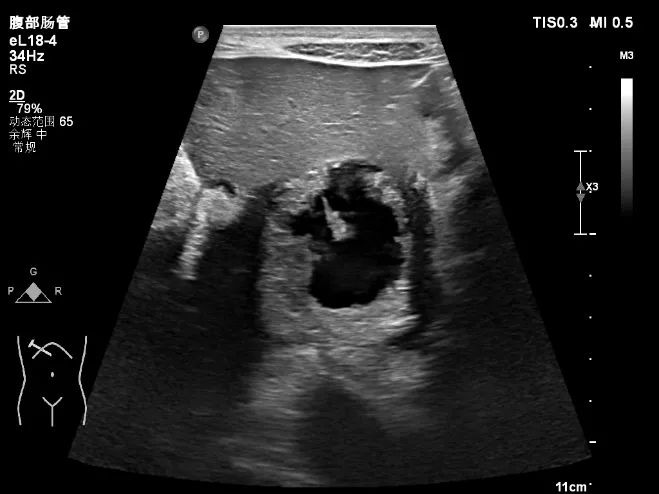

超声所示

肝脏体积增大,右叶斜径约 19.0cm ,肝内可见多个厚壁无回声,大的位于肝右叶,大小约 15.5cmx13.9cm 的囊实性结节,内可见粗大分隔及壁结节,肝内胆管未见扩张。CDFI: 囊肿周边可见少许血流信号(图 1-5 )。

图 2 去年 8 月肝内可见一巨大囊实性结节,内可见粗大分隔、厚壁及壁结节

图 4 囊肿周边可见厚壁,类似「 面包圈 」征